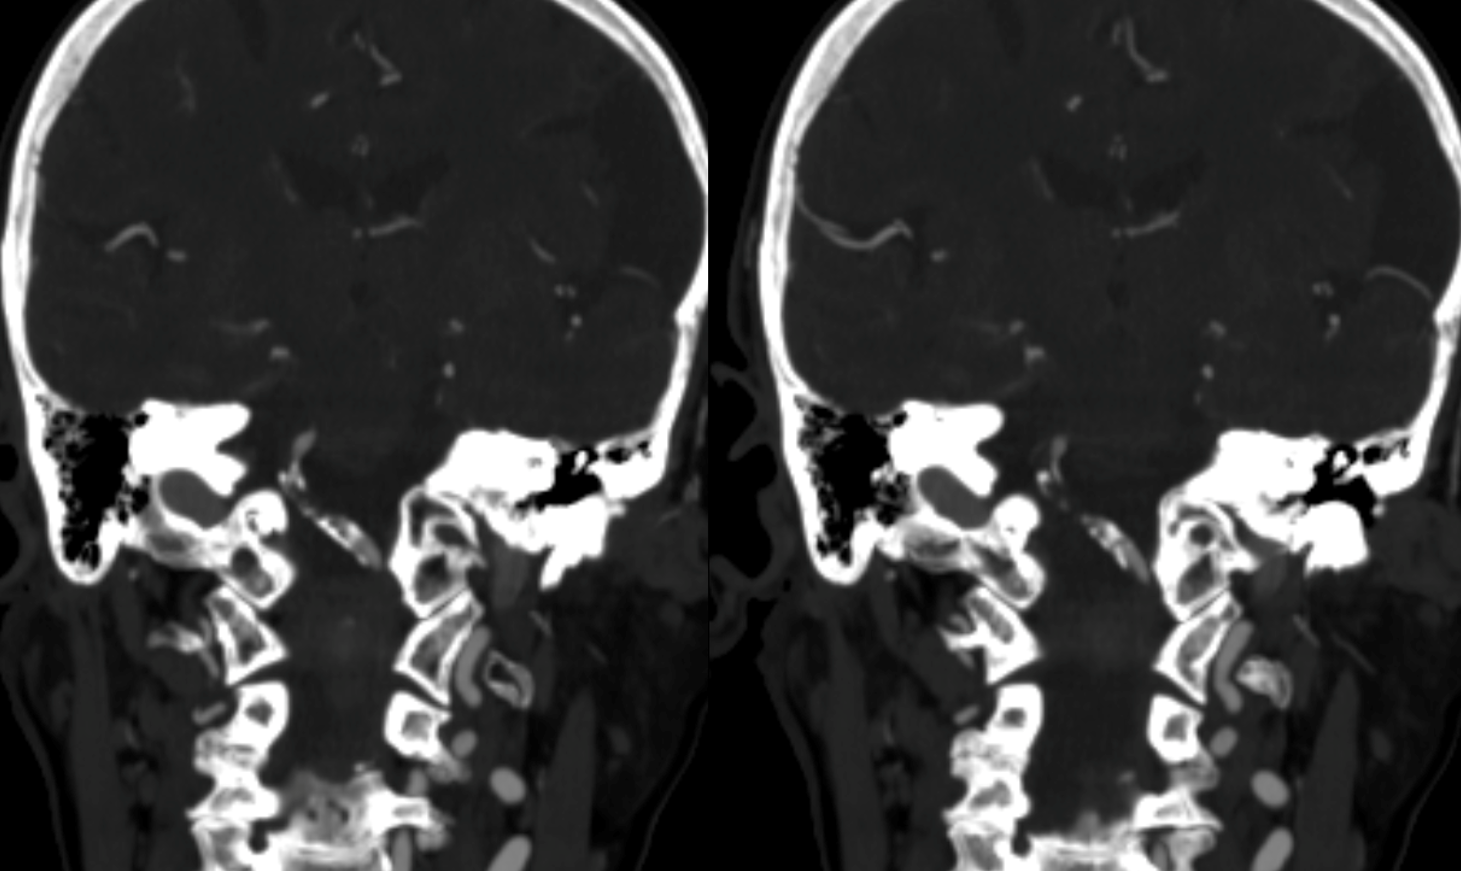

First angio

Small right PCOM

Unsuccessful Recan attempt